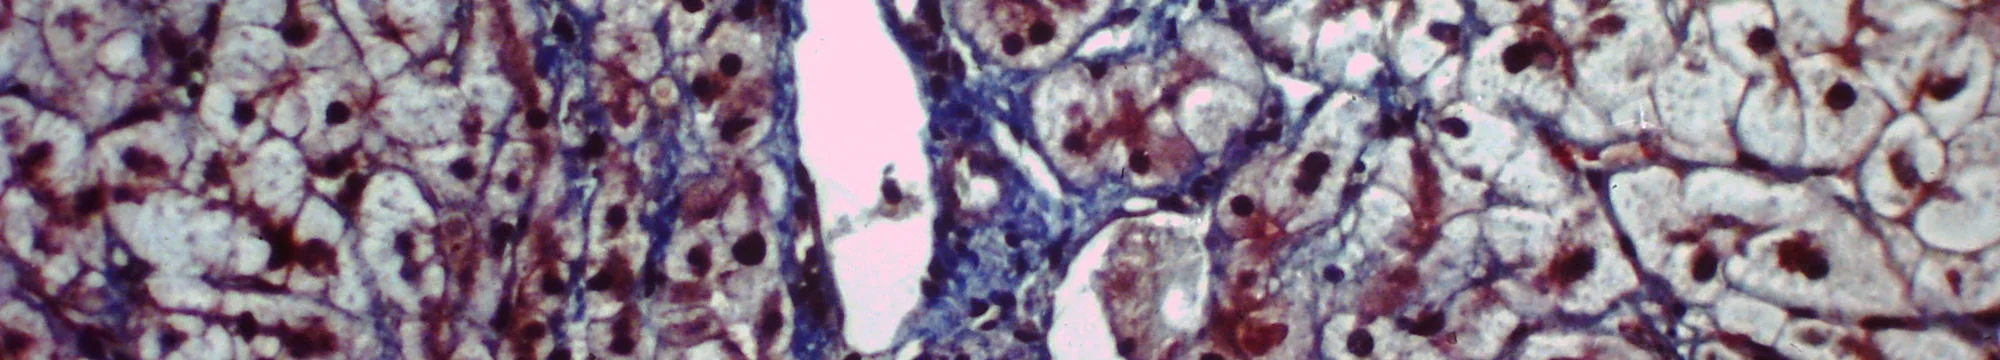

The objective of this study was to investigate the expression of selected interferon-stimulated genes (ISGs) in PBMC (peripheral blood mononuclear cell) prior and during the treatment with NS3/NS4A protease inhibitor faldaprevir plus pegylated interferon alpha-2a/ribavirin (PegIFN/RBV) in treatment-naïve and treatment-experienced chronic hepatitis C virus genotype 1 infected patients. This thesis was performed in three consecutive steps. First, we selected 95 most representative ISGs based on the literature. Secondly, we selected 30 patients for the SVR-oriented exploratory screening and tested all 95 genes in these patients. Finally, we tested 15 genes identified during the SVR-oriented exploratory screening in all patients eligible for this study (N = 263). As a result, we identified 15 genes which may play a role in the treatment response to faldaprevir plus PegIFN/RBV. Five ISGs (IFNA4, DDX58, IRF3, IFI27 and RSAD2) showed association with SVR at various time points. Baseline expression of two ISGs (IFNA4 and DDX58) was strongly associated with SVR. In conclusion, our data showed that the baseline expression of two genes (IFNA4 and DDX58) might be predictive of SVR in the treatment-naïve and treatment-experienced HCV GT1a and 1b infected patients treated with NS3/NS4A protease inhibitor faldaprevir plus PegIFN/RBV. Treatment-naïve patients had lower baseline expression of ISGs and more pronounced gene induction during the treatment as compared to the treatment-experienced patients. SVR patients had lower baseline expression and higher induction of ISGs during the treatment. IFNA4 and DDX58 should be considered for further investigations in prospective studies to confirm their predictive role for the treatment success of interferon-containing treatment regimens combined with protease inhibitors.